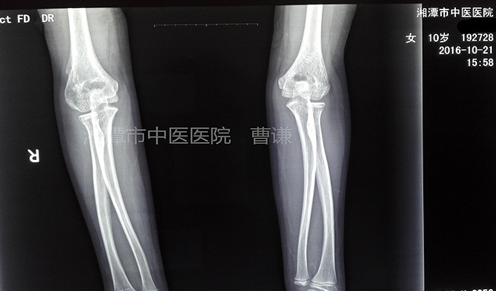

治療近三個(gè)月拍片復(fù)查,看上去是不是好多了?